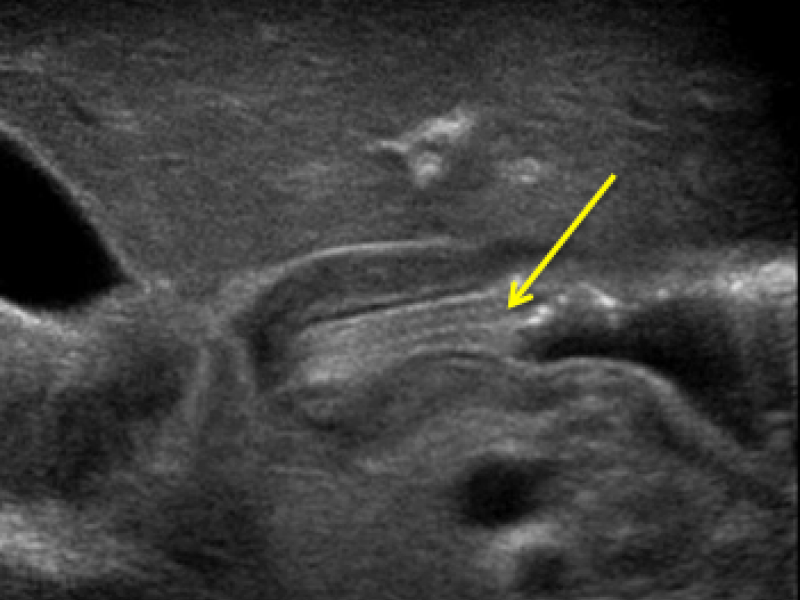

Imaging Case: Answer

Answer: False. Infants present with non-bilious vomiting